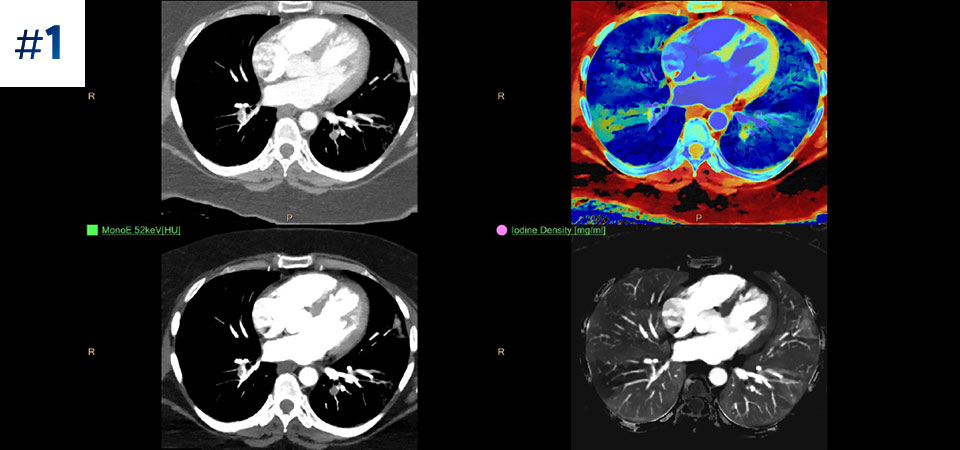

Permet une acquisition normale Une acquisition unique pour des données TDM classiques et spectrales rapides et à faible dose pour chaque patient, en toutes circonstances.

Est toujours disponible Acquisition entièrement spectrale et toujours disponible, même rétrospectivement, pour les résultats à la demande.

Réduction des examens de suivi L’amélioration de la caractérisation et de la visualisation des tissus peut réduire le besoin d’acquisition de suivi en cas d’examens sous-optimaux et de découvertes inattendues.

Allez au-delà de la TDM classique. Découvrez de quelle manière des couches de résultats issus de scanners à détection spectrale peuvent améliorer la fiabilité de votre diagnostic.